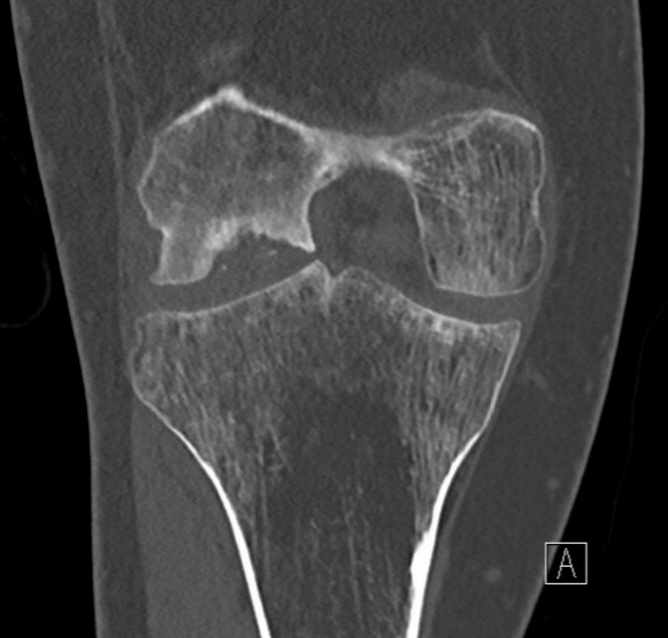

CT

Osteochondral defect